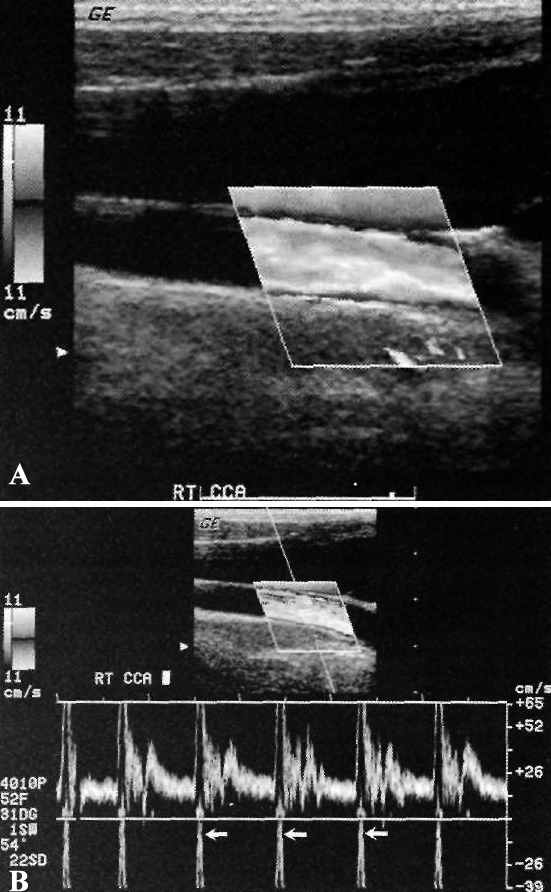

Допплерография сонной артерии: артефакт смешивания

Фото 8. Допплерография сонной артерии: артефакт смешивания. А – допплерограмма общей сонной артерии в норме: поток направлен в сторону датчика, на изображении должен быть красный цвет; так как поток имеет большую скорость и расположен центрально (белый и желтый), он превосходит размер положительной части допплеровской шкалы, поэтому оборачивается с отрицательной стороны. В результате поток визуализируется как направленный от датчика, как в прилежащей яремной вене. В – спектральная допплерограмма общей сонной артерии в норме: небольшая шкала скорости, нормальный пик систолической скорости превосходит размер шкалы и оборачивается вокруг, выходя снизу